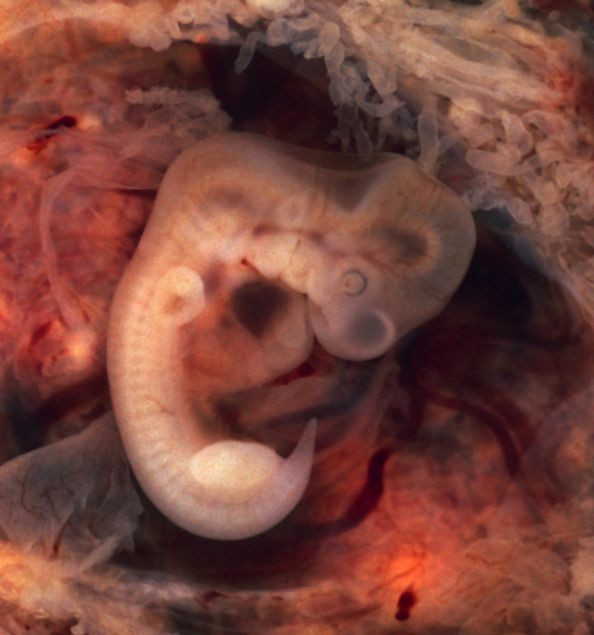

Saygın bilim dergisi Nature'da yayınlanan araştırma ABD'deki Oregon Üniversitesi'nde Amerikalı, Çinli ve Güney Koreli doktorlar tarafından yapıldı.